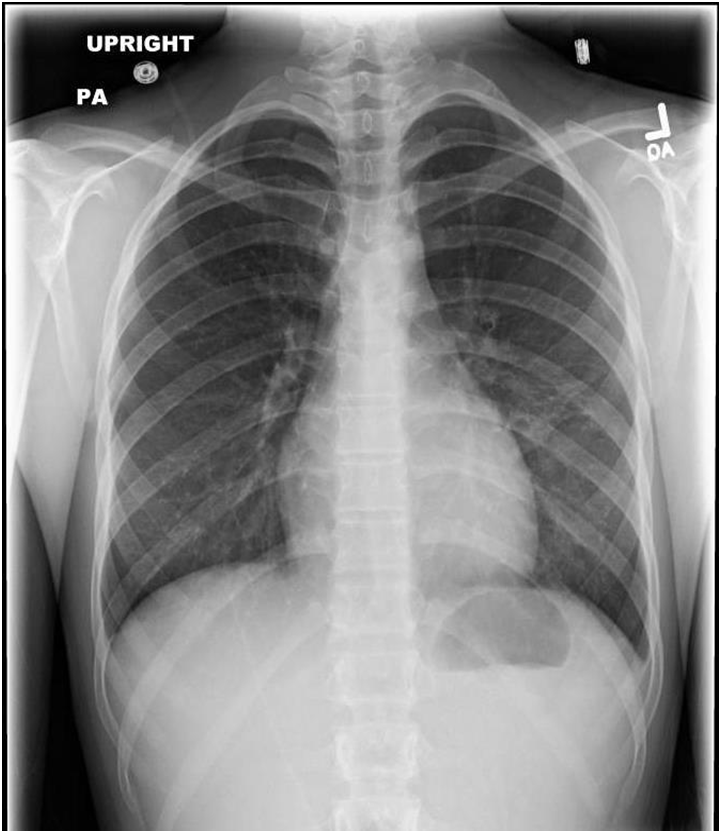

ECG revealed sinus tachycardia and right axis deviation without ST-T changes (Figure 1.). Laboratory studies, summarized in Table 1, revealed a mild normocytic, normochromic anemia and a considerably elevated serum troponin I level. Chest radiography (Figure 2) revealed a non-specific mild left perihilar/lingular area of atelectasis or infiltrate. Given her history of fever, the patient underwent technetium labeled white blood cell (WBC) scanning, prior to the onset of her chest pain, which revealed intense labeled WBC uptake at the left ventricular myocardium consistent with myopericarditis (Figure 3). A transthoracic echocardiogram (Figure 4) revealed normal right and left ventricular (left ventricular ejection fraction of 55-60 %) and a small pericardial effusion.

Figure 2 Chest radiography.